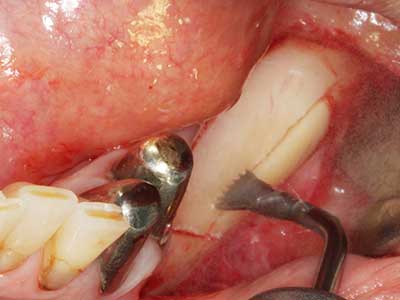

За отстраняването на имплант, вестибуларното костно покритие, което е заменено след премахване на импланта, може да бъде оформено, за да задържи контура на алвеоларния гребен.